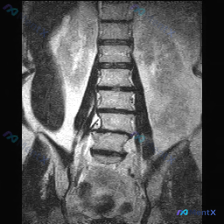

整理到一份腰椎冠状位MRI影像资料,先给大家看客观表现: - 脊柱力线:腰椎向右侧侧弯 - 椎体:高度、排列大致连续,无明显滑脱,骨质信号未见明确局灶异常 - 椎间盘:普遍T2低信号(脱水退变),下腰椎(L3/4-L5/S1)椎间隙变窄,冠状面见轻度周边膨隆 - 小关节:多节段骨质增生、间隙窄,呈退...